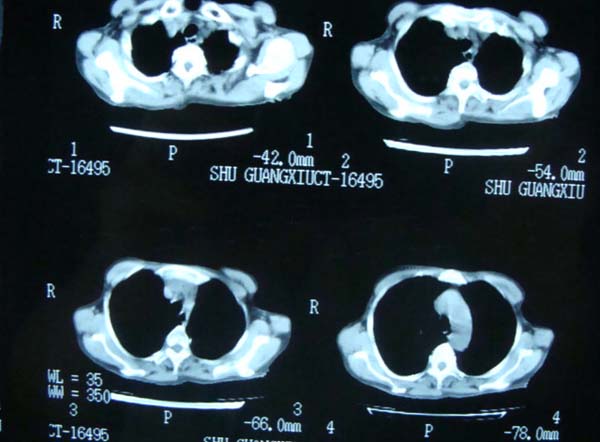

以下是引用老爱克斯新网客在2008-6-2 6:38:00的发言:[br]ct表现是肺动脉根部明显扩张,右心室增大,左房左室及右房都不大,因此可以除外风心。高血压心脏病。冠心病。定位片基本可以除外肺心病,(心肌病。心包积液更不可能)因此除外了后天性获得性心脏病。其表现也可以除外室缺。房缺。动脉导管未闭等常见的先心病。如果是原发性肺动脉高压除肺动脉根部扩张外双侧肺动脉尤其是右下肺动脉干应该也有扩张。因此我认为最大的可能是肺动脉瓣狭窄伴有窄后扩张,建议做一下彩超就知道了。期待结果。